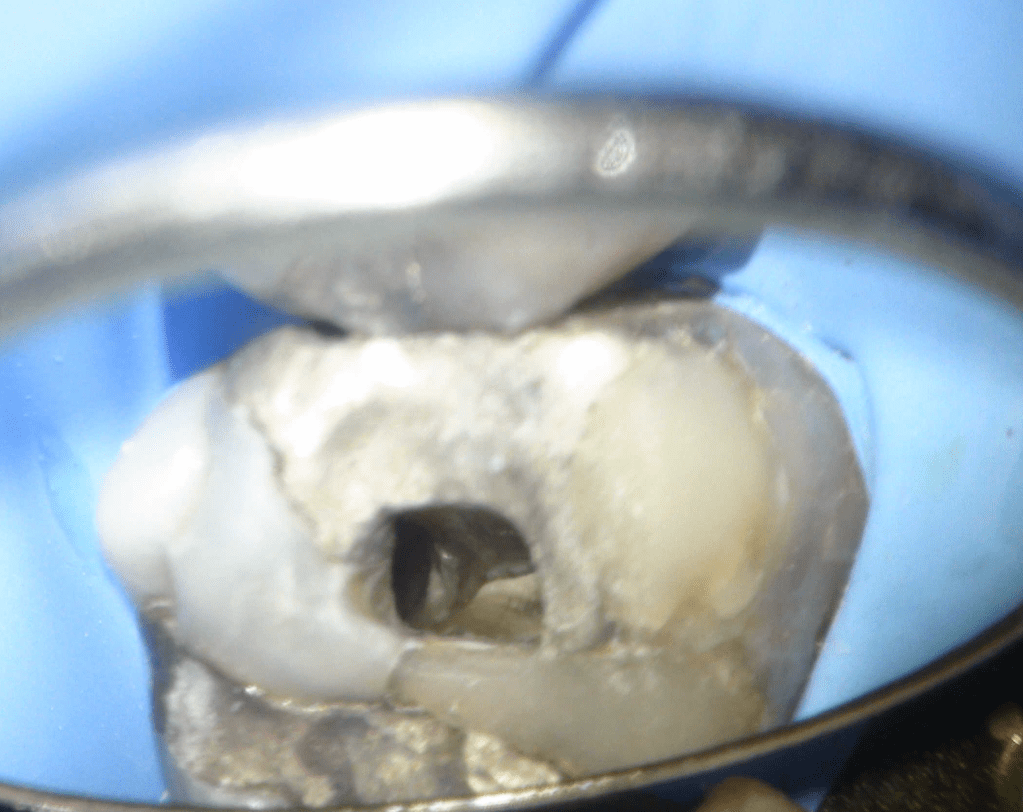

Fisura, remoción amalgama para explorar